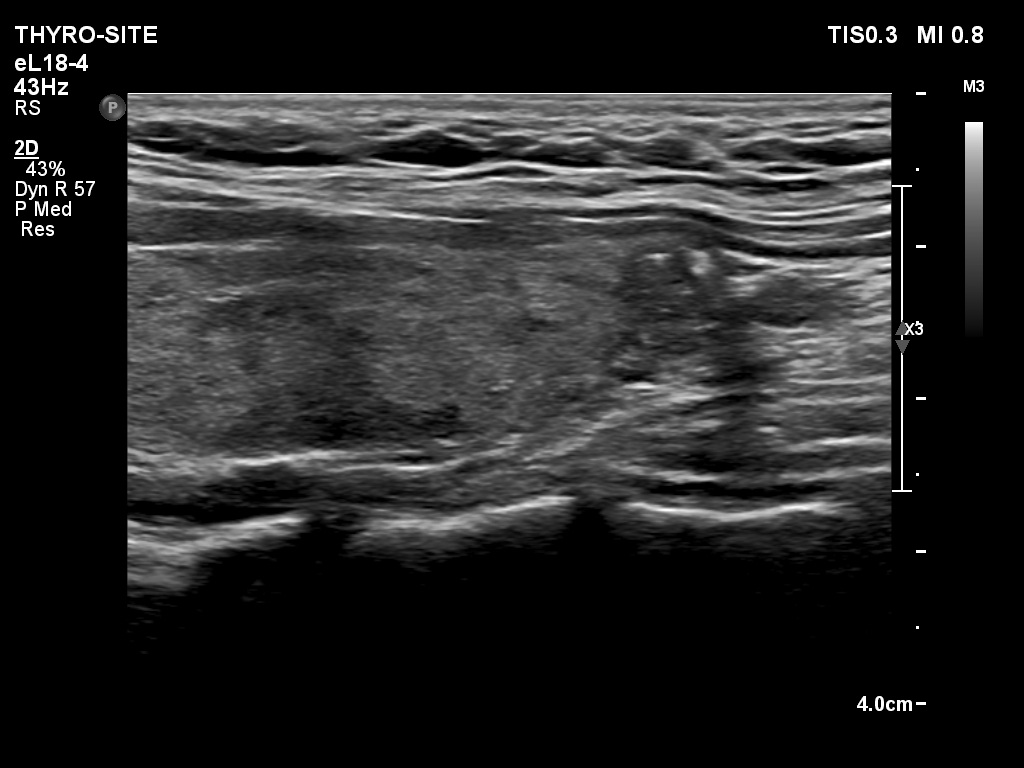

Differentiation of discrete lesions - case 1483 (ultrasonographic picture 8)

Left lobe, longitudinal scan. The lesion in question has lobulated margins. The lobe contains other hypoechogenic areas corresponding to the underlying Hashimoto's thyroiditis.